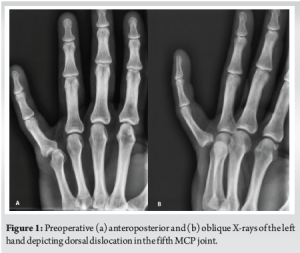

A 48-year-old male presented to the Emergency Department (ED) of our hospital with a left-hand injury sustained during a soccer match, caused by being kicked by an opponent. Clinical examination revealed pain, deformity, and restricted range of motion in the little finger. The patient had no significant medical or surgical history and reported no paresthesia. Sensation and capillary refill time were normal in the affected finger. Radiographs (anteroposterior [AP], oblique views) depicted a dorsal dislocation of the metacarpophalangeal (MCP) joint (Fig. 1). Close reduction was attempted twice in the ED without success. The patient was informed about the need for surgery and taken to the operating room.